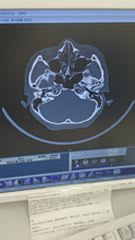

中央病院へ行き検査をしてもらったら

鼻の骨が折れてました